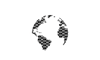

Dr. Malcher | Robotic repair of incarcerated inguinal hernia using CO2 asperation tip

Doctor(s): Dr. Malcher Description of of the case: Robotic repair of incarcerated inguinal hernia using CO2 asperation tip Products Used: Ventralight™ ST Mesh [...]